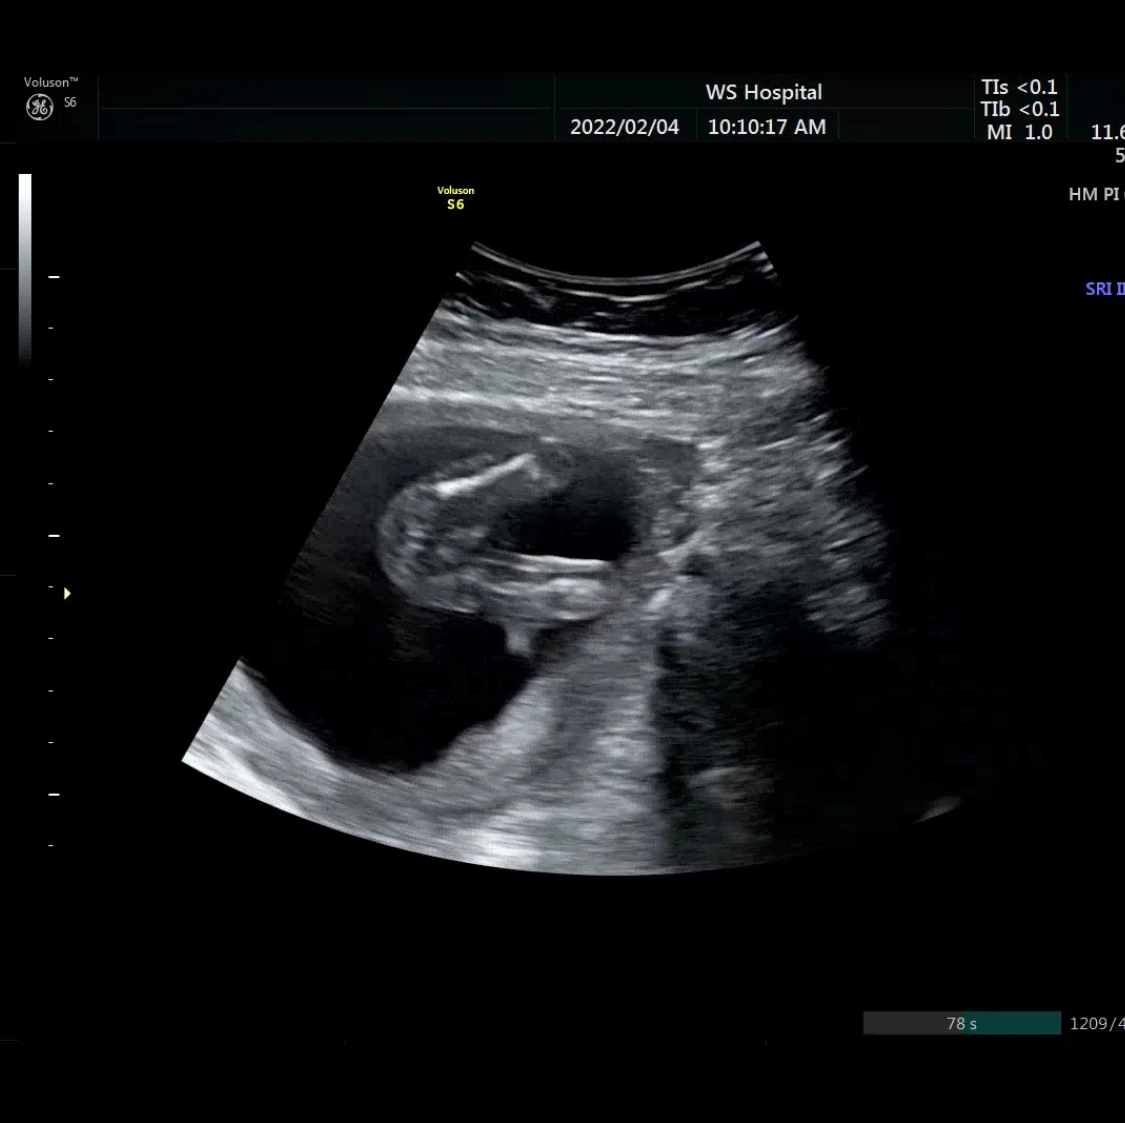

내 몸 속 다른 생명체를 처음으로 감지하게 되었을 때, 그 감촉은 물고기같았다. 여린 꼬리가 나의 안쪽 어딘가를 훑고 지나가는 감각이었다. 그것은 내가 미쳐 캐치하지 못했던 기포의 주인이었다. 이윽고 그것에 손과 발이 달리고 늘어나서, 내 배를 밀어 재끼기 시작할 땐 몸에 예상치 못한 곡선이 튀어나왔다. 침을 질질 흘리며 한순간에 튀어나오던 에일리언의 리플리처럼, 시고니 위버마냥 강인한 여성이 될 수 없었던 나는 잠도 못자고 밤새 뒤척였다.

어쩌면 그것은 전설 같은 기분이다. 두 가지 이유가 있다. 첫 번째는, 임신하기 전까지는 이해 못할 감각의 언어들로 이루어져 있다는 것이다. 물고기며 기포라니, 나의 설명이 감각으로 이해 되는가? 태동이 심한 아이가 배에 장풍을 찍고, 발가락을 셀 수 있을 정도로 찬다는 걸 믿을 수 있을까? 임신을 하고 난 후 난 그것이 허풍이 아닐 가능성에 대해 고려해보았다.

태동이라는 것은 적어도 걱정, 많아도 걱정인 부분이 있다. 첫째는 유독 태동이 없어서 마음을 조리게 했다. (밖으로 나온 녀석은 5초도 가만히 서 있지 못한다) 달콤한 것들을 삼키며 움직이길 한참 기다리는 날도 많았다.

그 때 고요하던 녀석이 힘차게 움직였다. 부드럽게 지나가던 감촉을 기억한다. 토닥토닥, 괜찮다는 듯이, 혼자가 아니야, 이제 내가 너의 삶에 있어, 앞으로는 절대 외롭지 않아, 라고 말하듯이. 온통 몸을 옥죄어 오던 고통의 감각은 어느새 위로의 감촉이 되었다. 몸 안으로 전해지는 이물감은 어느새 절대적인 고독을 지우는 상냥한 터치가 되었다.